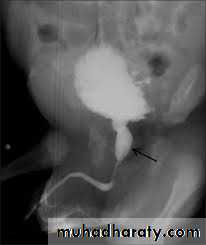

Posterior urethral valve